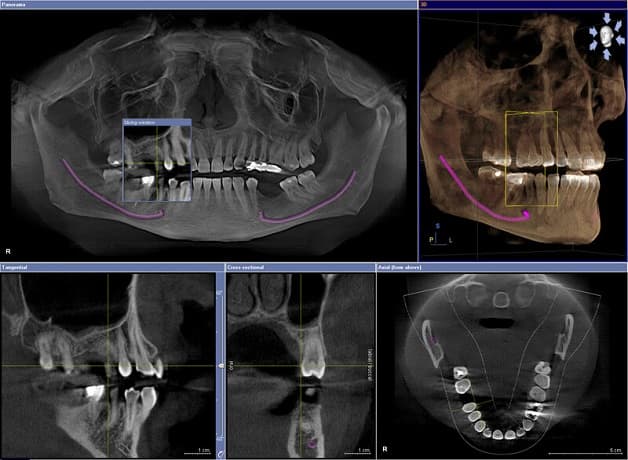

Kết quả chụp cắt lớp vi tính răng có độ chi tiết cao, tương phản hình ảnh đẹp và sắc nét. Bác sĩ có thể quay, căn chỉnh các hướng khác nhau để quan sát rõ hơn hình thái, cấu trúc răng, cấu tạo xương hàm và vị trí ống dây thần kinh để có thể đưa ra phác đồ điều trị tốt nhất cho bệnh nhân.

Hình ảnh chụp cắt lớp vi tính răng.